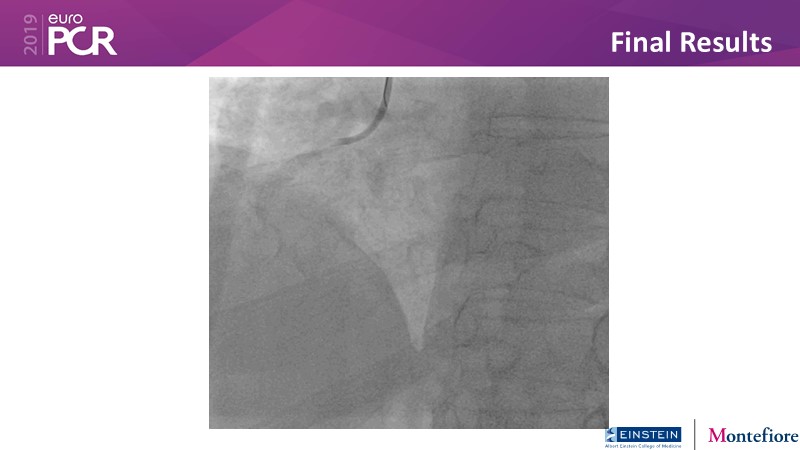

Consult this session to get insights about the need for a dedicated drug eluting stent (DES), as well as the benefits of a DES+DCB strategy, for diabetes mellitus (DM) and acute MI (AMI) patients.

- To understand and learn benefits of DES+DCB strategy to provide uniform and homogenous drug delivery in patients with diabetes mellitus and acute MI